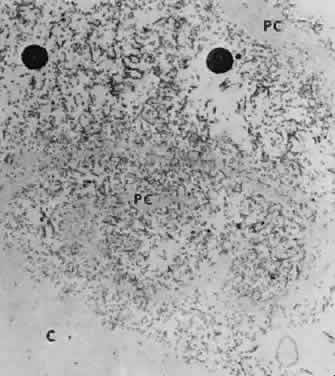

Accumulation of exfoliative material may be detected histopathologically throughout the anterior segment to include the lens, iris, trabecular structures, conjunctiva, ciliary body, and zonules. The deposition of fibrillar eosinophilic material on the anterior lens capsule is the classic histopathologic feature of XFS (Fig. 9). Ultrastructural studies also indicate some degree of actual exfoliative changes or peeling of the anterior lens capsule74 (Figs. 10 and 11). In addition, Ashton and associates describe a degenerative band containing exfoliative material within the inner half of the lens capsule.5 Bertelsen and coworkers independently noted projection of coarse fibrils from the lens surface into the deep portion of the lens capsule to form an amorphous layer of the lens capsule between the lens epithelium and normal lens capsule.6 Thus, studies indicate that exfoliative material accumulates on the anterior lens surface but also that the lens capsule itself may be involved, and that the underlying epithelial layer may at least partially contribute to the production of the exfoliative material.

Fig. 10. Scanning electron micrograph showing layer of anterior lens capsule and exfoliative material (PC) peeling back from rest of capsule. Asterisks indicate exfoliative vegetations (× 5340). (Dark AJ, Streeten BW, Cornwall CC: Pseudoexfoliative disease of the lens: A study in electron microscopy and histochemistry. Br J Ophthalmol 61:466,1977)

Fig. 11. Transmission electron micrograph of peeling lens capsule (PC) rolled up in spiral, enclosing masses of exfoliative fibers and two melanin granules. C, main capsule (× 14,600). (Courtesy of Dr. Barbara Streeten)

Exfoliative material consists of an irregular meshwork of fibers composed of fibrillar subunits.74,92 Masses of these fibers correspond to the material seen clinically (see Fig. 10). The individual fibrils, which measure 6 to 8 nm in diameter and exhibit cross-banding at 10- to 12-nm intervals, are hypothesized to consist of macromolecules with a protein backbone and polysaccharide side chains.93–95 In contrast to collagen, the amino acid content of exfoliative material lacks hydroxyproline.96 Ringvold and Husby noted histochemical, immunologic, and ultrastructural features that led them to classify exfoliative material as an amyloid-like substance.97 Repo and associates note Congo red-positive staining for amyloid in the vessel walls of 7 of 13 iris specimens from exfoliation patients and believe that these findings support the theory that XFS is associated with amyloid.59 Immunohistochemical studies by other investigators show heparin sulfate and chondroitin sulfate proteoglycans, laminin, entactin/nidogen, fibronectin, and amyloid P protein to be components of exfoliation material.98,99 Schlötzer-Schrehardt and coworkers suggest that the material may be an expression of a disordered extracellular matrix synthesis.98